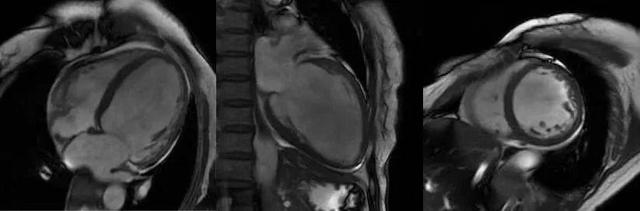

心脏磁共振被称为心脏“一站式”检查,通过多参数成像能够对心脏的结构、功能、室壁运动、心脏瓣膜、心肌灌注和活性进行“一站式”评估。主要通过电影序列(短轴、两腔心、四腔心、三腔心)、T2WI序列、首过灌注序列以及延迟强化序列对心脏进行综合成像。